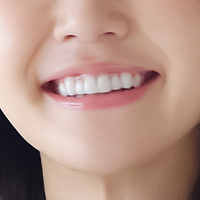

<術前>

<術後>